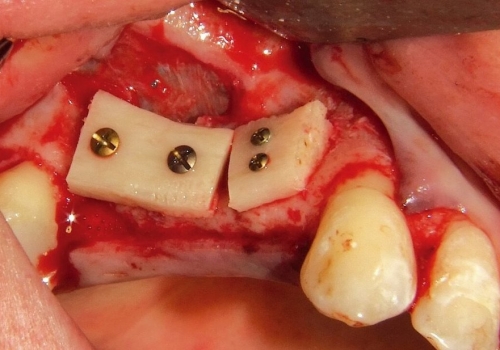

Bərpa texnikasının müəyyən edilməsi, sümüyün hansı bölgədə, hansı miqdarda itirilmiş olmasına bağlı olaraq müəyyənləşdirilir. Bərpa üçün tətbiq edilən sümük materialları pasiyentin öz donor bölgələrindən xüsusi metodlarla qazanılmış sümüklər, o cümlədən digər fərdlərdən alınmış və xüsusi qaydada hazırlanmış materiallar, heyvan mənşəli sümükəvəzləyici materiallar və sintetik materiallar olaraq ayrılır.

Bərpa zamanı yerinə görə bu materiallar ya ayrı-ayrılıqda, ya da kombinə olunmuş şəkildə tətbiq oluna bilir. Gündəlik təcrübədə həmçinin pasiyentdən götürülmüş qan nümunələrindən alınmış yüksək bərpaedici xassəyə malik materiallar (PRF) da uğurla tətbiq olunur. Sümükartırma metodlarının tətbiqi sayəsində, çənədə implantların yerləşdirilməsi üçün yetərsiz sümük həcmi olan bölgələrdə sümük miqdarı yetərli duruma gətirilir, uyğun boy və diametrə uyğun implantlar uğurla tətbiq olunur.